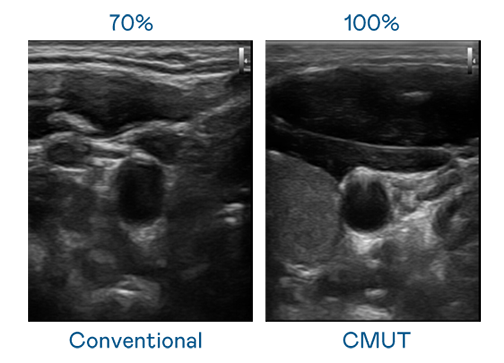

CMUT 技术是一种用电容式微机电元件来产生超音波讯号的技术。与传统 PZT 压电式技术相比,CMUT 频宽增加 30%,更宽频的超音波讯号让影像解析度大幅提升,是实现高影像品质医疗超音波扫描、促进精准医疗发展的关键技术。

大频宽带来超清晰影像

超音波影像的解析度高低,首先取决于探头能发出的讯号频宽。8040威尼斯 CMUT 可提供高清晰的超音波讯号,提供高频宽、高灵敏度、影像纹理细节更高的超音波影像,协助医护人员缩短影像判读时间及利用精准的医疗影像进行诊断。